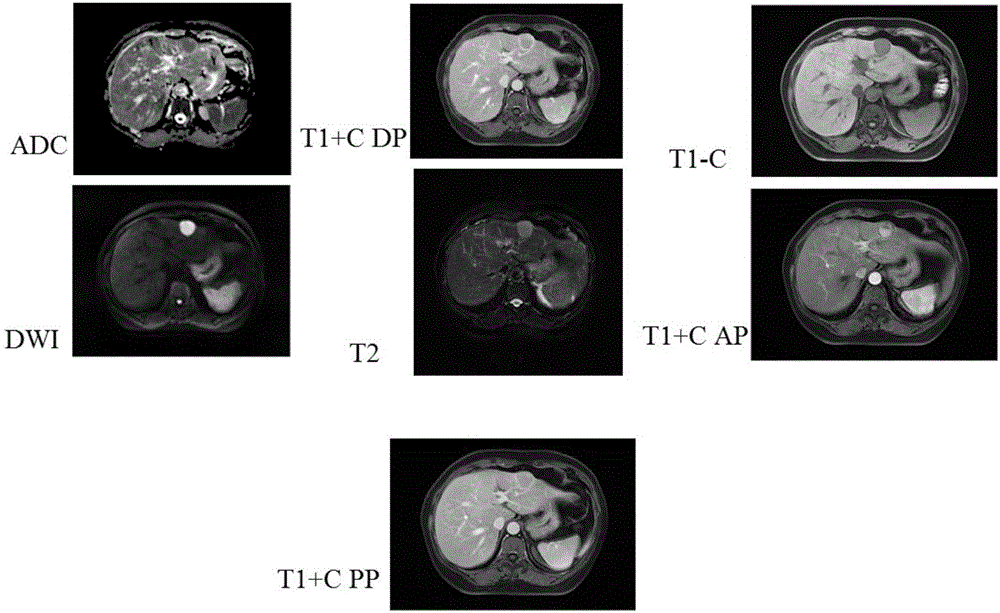

图片来源:医影维度